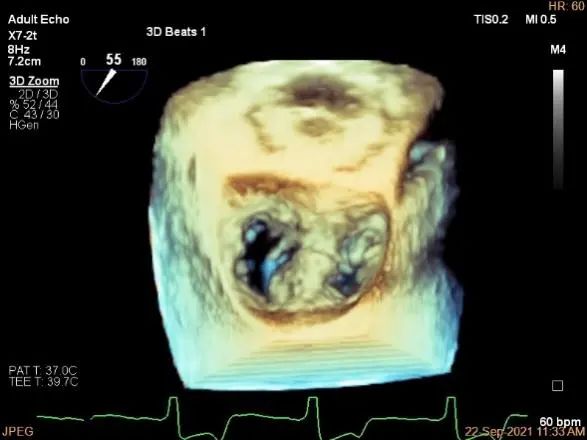

术中超声

3D:P1区脱垂并腱索断裂,Width:11.4mm

3D-color:重度MR,4级

3d确认夹子位置在P1区